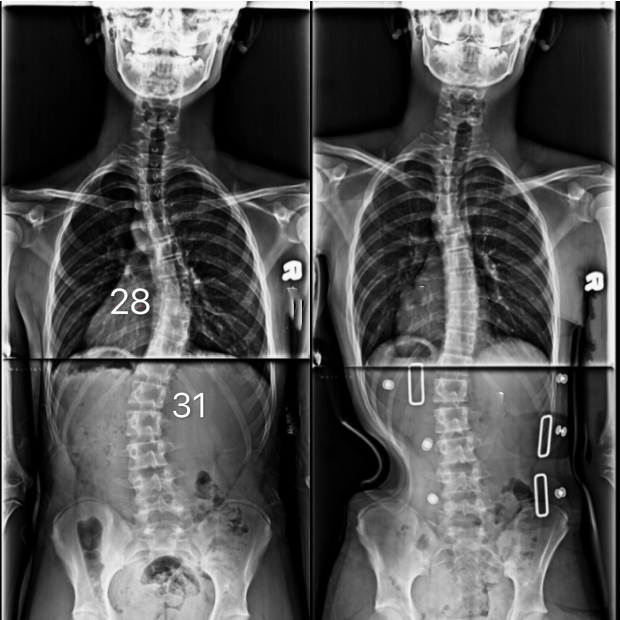

胸彎28度,腰彎31度

16歲脊椎側彎男孩